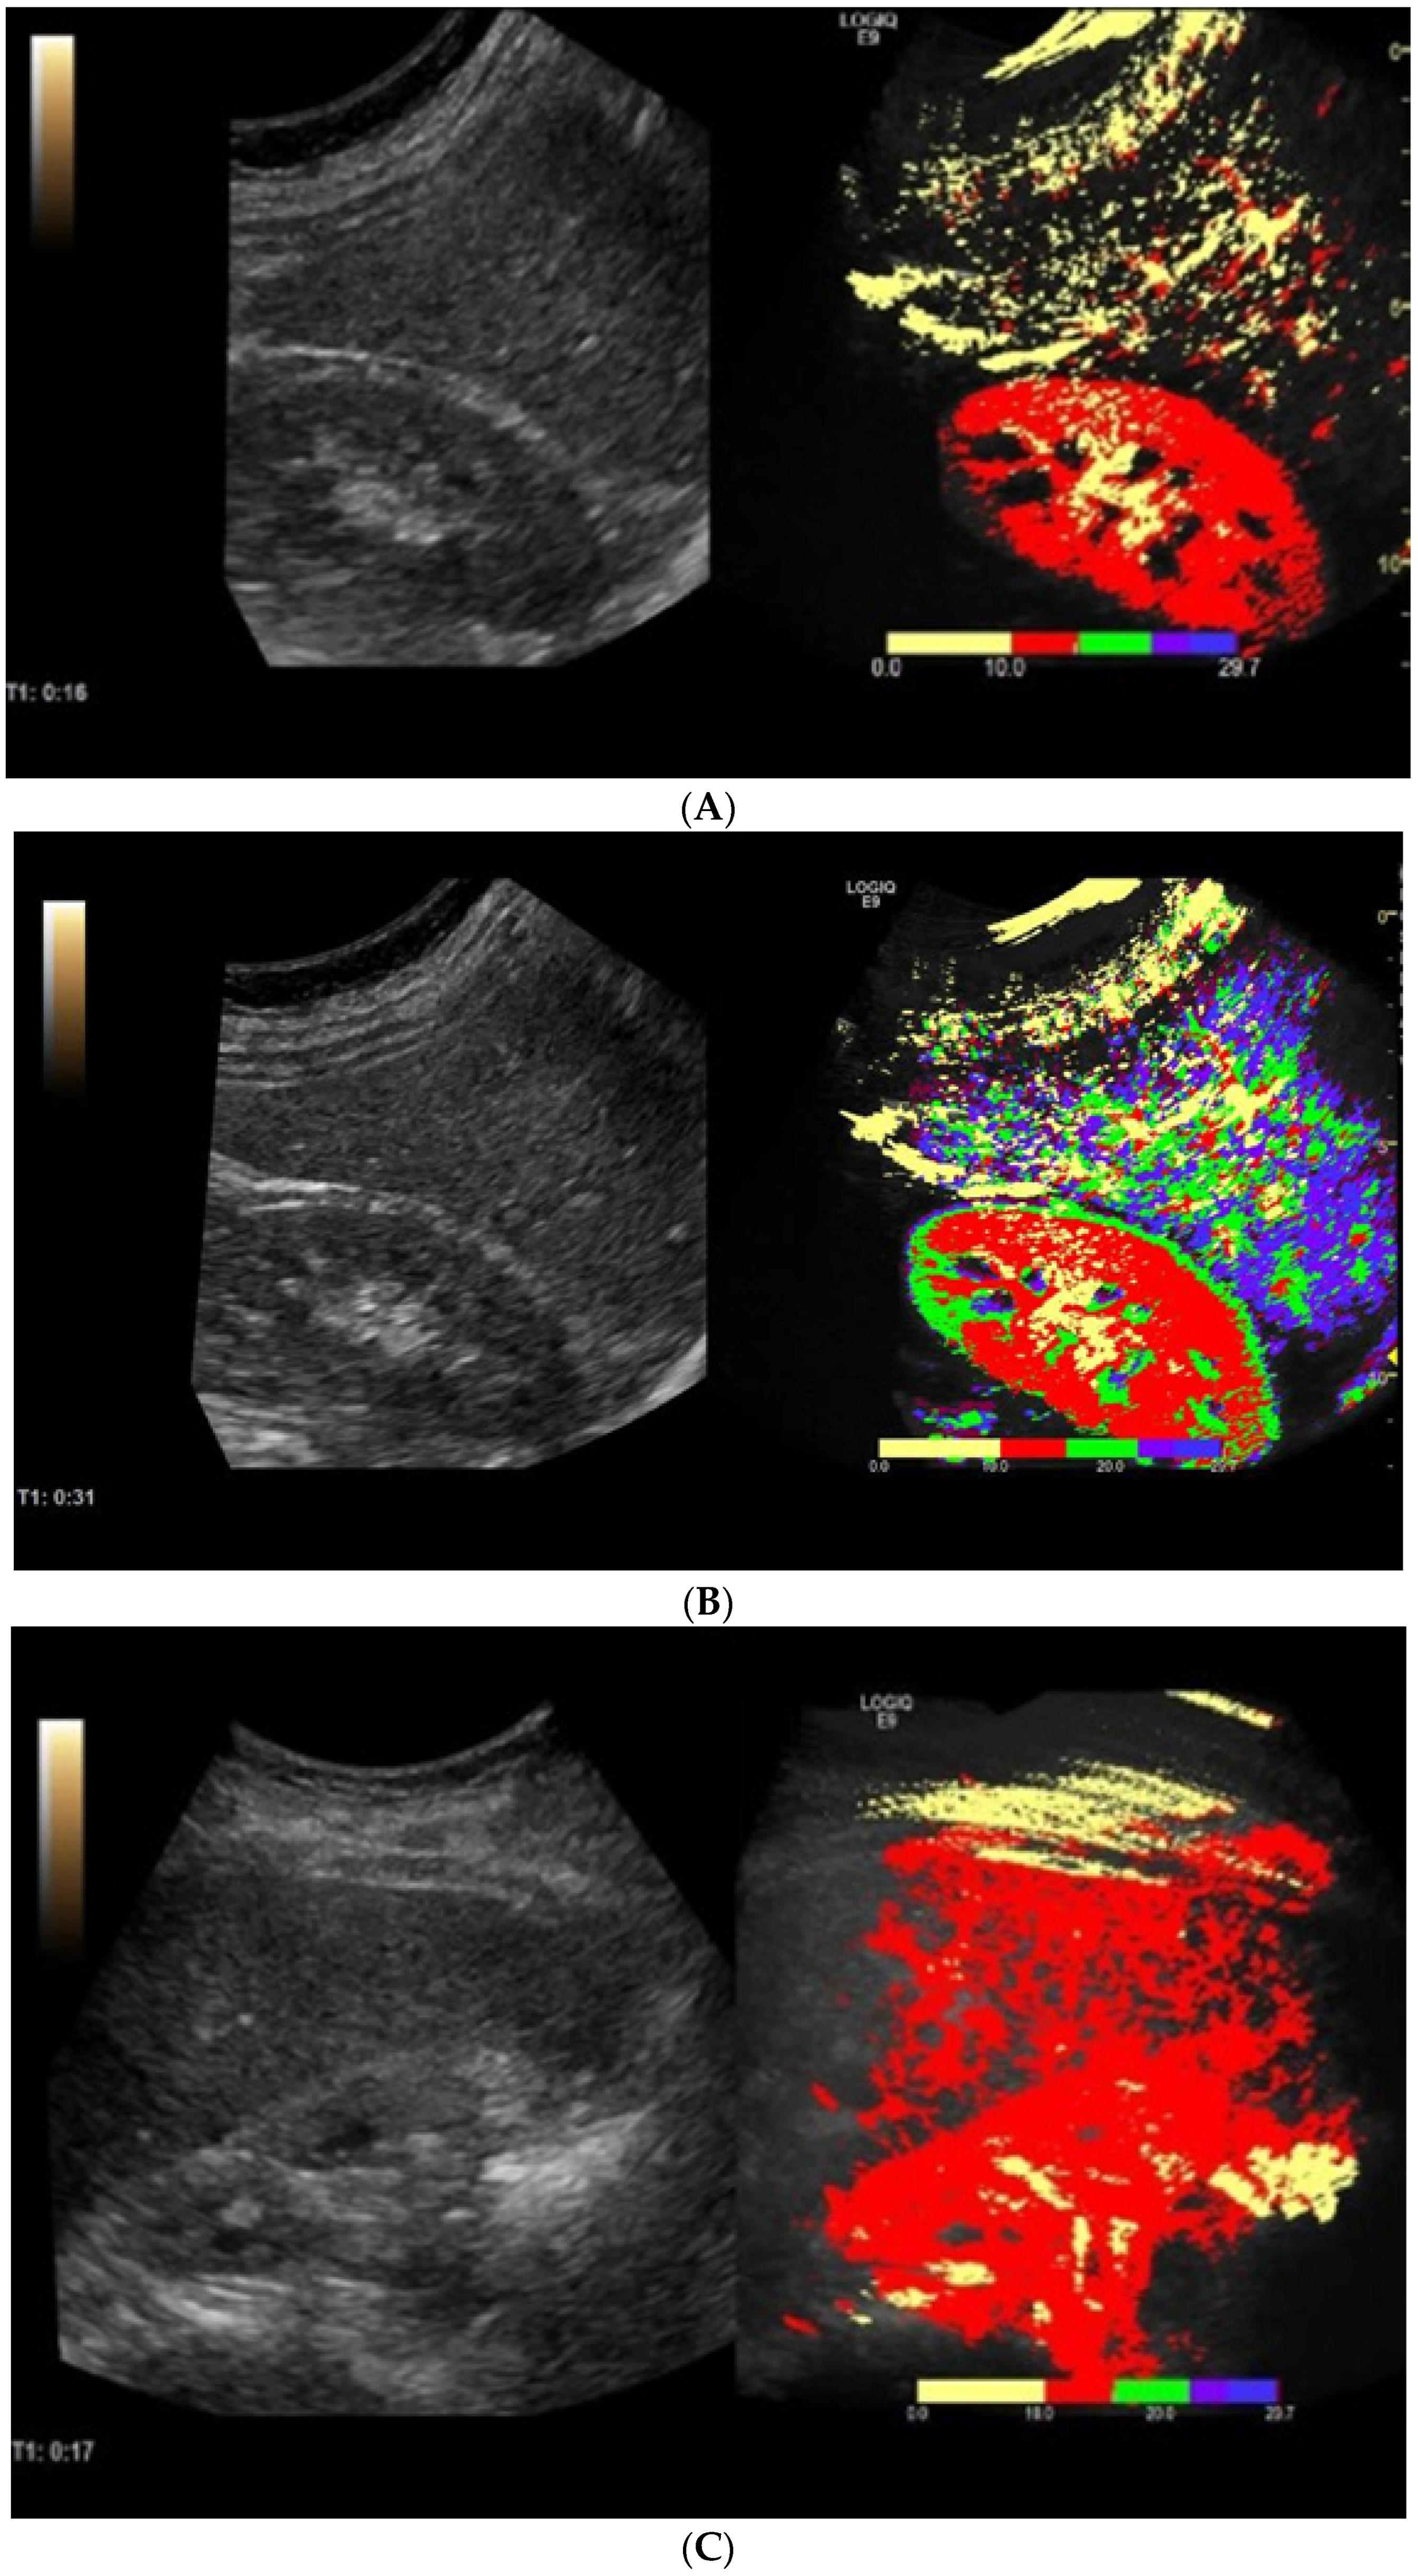

2.3. Contrast-Enhanced Ultrasonography with Arrival Time Parametric Imaging